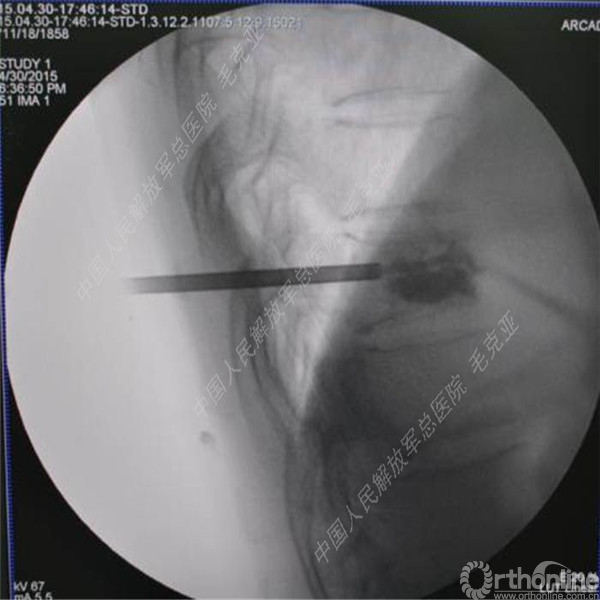

导语:随着社会老龄化的不断加速,骨质疏松性椎体压缩骨折作为一种普遍存在的老年骨科疾病已经成为现今骨科界的一个热点话题。传统的保守疗法治疗效果不佳,而现有的椎体增强技术又具有多种风险和缺陷。针对这种现状,中国人民解放军总医院毛克亚教授提供了一种新的解决方法。